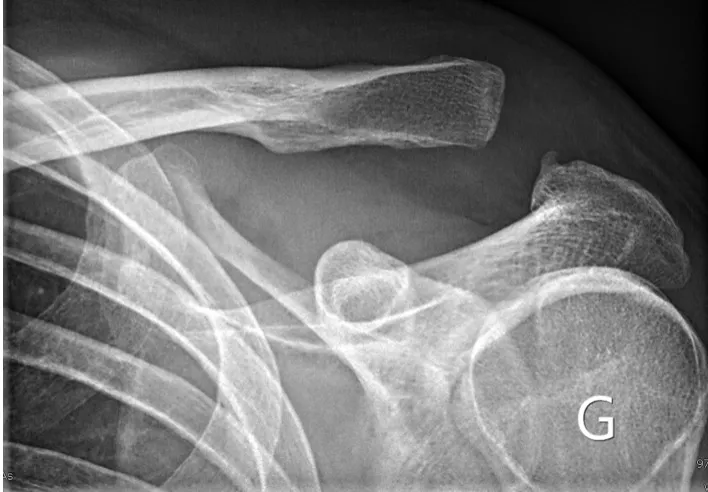

Dans un premier temps des radiographies permettent d'avoir une orientation diagnostique en corrélation avec l'examen clinique du chirurgien. Des clichés comparatifs (des deux épaules) permettent d'affiner le diagnostic. Un scanner avec des reconstructions tridimensionnelles peut être utile dans certains cas.